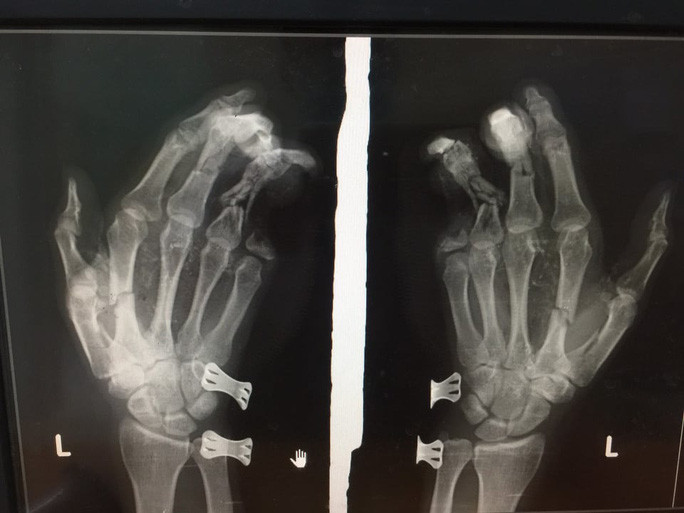

Điện thoại đang sạc phát nổ, thiếu niên dập nát 2 bàn tay: Ngày 19/12/2020, Phạm Đức L. (SN 2005, xã Nghĩa Lộ, Yên Bái) đã được gia đình đưa đi bệnh viện trong tình trạng bàn tay phải bị dập nát, mất hoàn toàn ngón 1, cụt đốt 2, 3 (ngón 2, 3) cụt ngón 4, 5; bàn tay trái nham nhở, dập nát phần mềm; gối phải bị thương chảy máu; vùng mặt, mắt tổn thương, cằm bị rách. Nguyên nhân L. nói là khi đang dùng điện thoại bỗng dưng phát nổ. (Ảnh Người lao động)